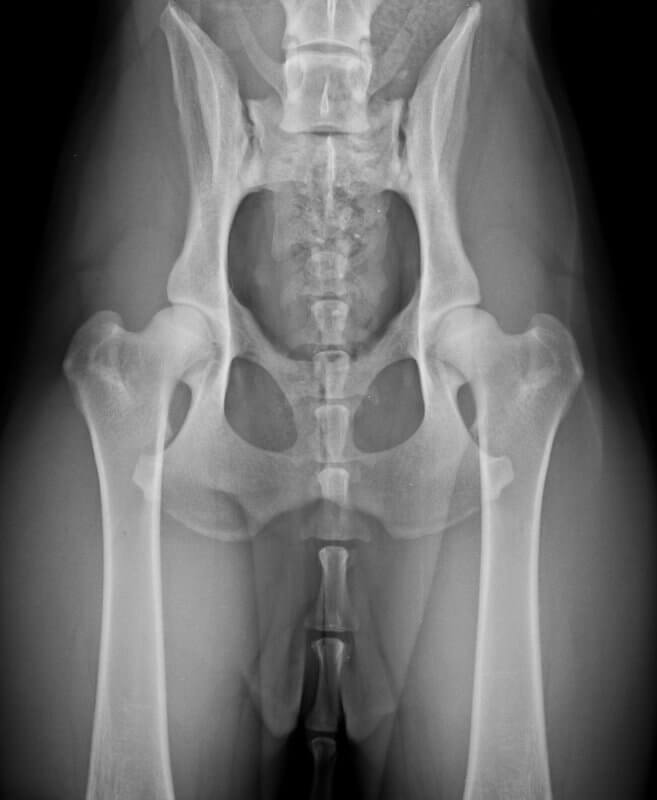

• So richtig beurteilen kann man das nur wenn die Auswertungsschablone auf die Aufnahme gelegt wird, denn u.a. ist ausschlaggebend wie tief die Hüftkugeln in den Pfannen drin sitzen. Wenn man nur mit dem bloßen Auge schaut kann man sich da manchmal täuschen. Da vertut sich sogar Dr. Tellhelm manchmal bezüglich der Beurteilung des Norberg-Winkels mit bloßem Auge und muss seine erste Aussage korrigieren sobald er die Schablone angelegt hat.

Ich hänge Dir mal ein Bild einer "normalen" Hüfte an. Du kannst dann auf der Aufnahme Deines Hundes besser erkennen wo die Schwachstellen liegen. So sitzen die Hüftkugeln nicht so tief in den Pfannen drin wie bei einer "normalen" Hüfte. Dadurch ergibt sich dann ein schlechterer ( = geringerer) Norberg-Winkel und ein größerer Gelenkspalt. Die Konturen/Ränder von Pfannen und Kugeln bilden sich bei einer "normalen" Hüfte scharf ab, Pfannen und Kugeln sollten gleichmäßig und "deckungsgleich" ( = kongruent) ausgebildet sein. Bei der Aufnahme Deines Hundes erkennt man vor allem rechts dass sich die Konturen nicht scharf abzeichnen sowie Kugel und Pfanne nicht gleichmäßig und kongruent ausgebildet sind.

Die Qualität der Abbildung lässt jetzt keine Aussage zu ob sich am Hüftgelenk evtl. bereits irgendwo eine beginnende Arthrose zeigt. Auch das kann zu einer Abstufung führen. Die Nuancen liegen dabei aber im Millimeterbereich, so dass man das nur auf der Originalaufnahme beurteilen können wird.